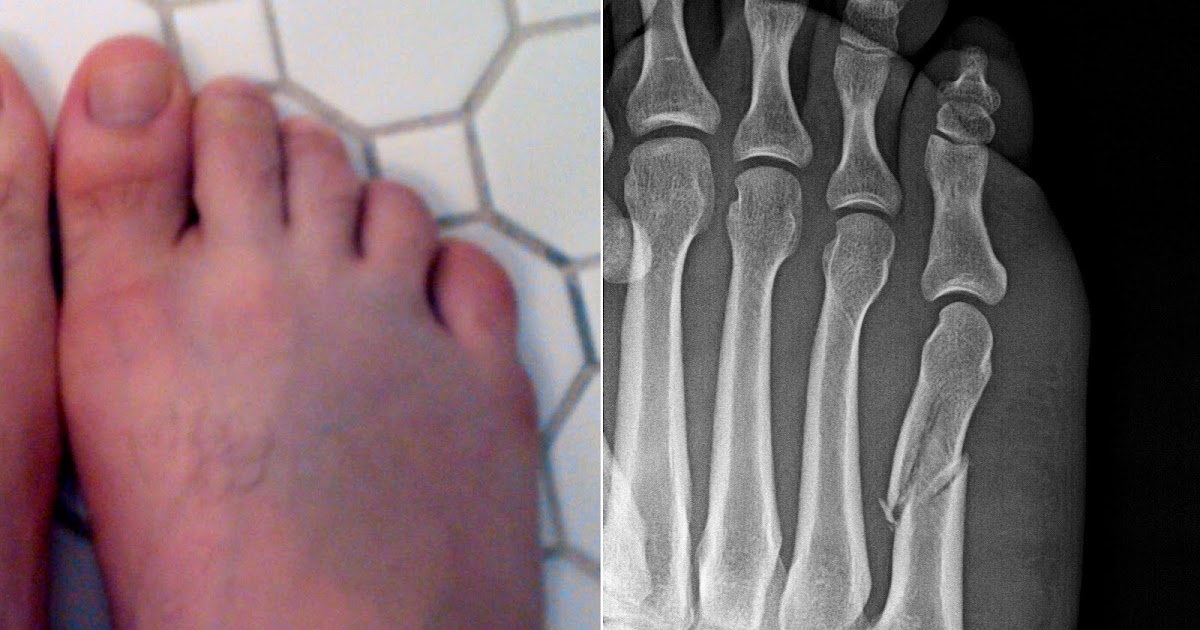

Types Of Broken Foot Injuries. the most common causes of an injured foot include falls, crush injuries (including impacts from a heavy object or an automobile accident). All foot fractures, even small ones, require a visit with a healthcare provider for proper diagnosis and treatment.  — a fractured foot can be caused by trauma from a sports injury, fall, or other accident. Broken foot treatment may involve rest, applying ice, elevating the foot, taking. while every fracture is severe and requires prompt medical attention, seven types of foot fractures are the most prevalent. sports injuries, accidents and falls can all lead to a broken foot. lisfranc injuries — whether or not you have a fracture — often have the following symptoms on or near the top of your foot:.  — for a broken foot, basic questions to ask include: What tests do i need? You can also break a bone through overuse or repetitive stress.  — break or strain?